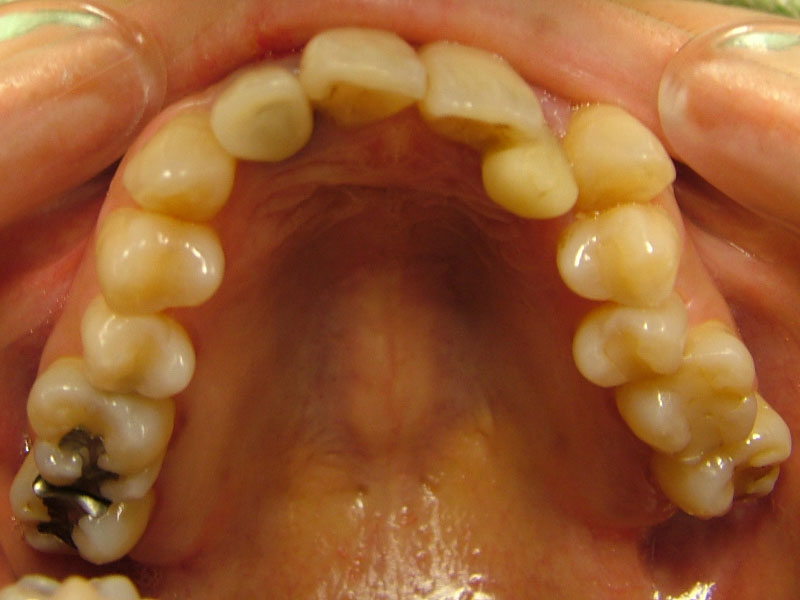

術前

• 初診:2006年、2014年―矯正治療を含めた一口腔単位の治療開始、治療当時、30代女性、非喫煙者

• 主訴:できれば歯並びを良くし歯を白くしたい。

• 治療方針:親知らず3本抜歯、上下小臼歯4本抜歯、矯正用インプラント使用のワイヤー矯正、修復処置、保定(上マウスピース、下ワイヤー)、メンテナンス